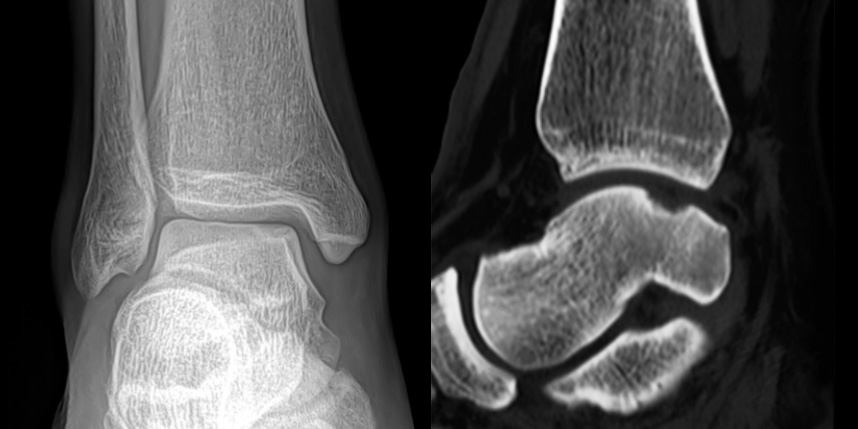

연골손상의 단계를 결정할 때 사용하는 ICRS 단계에서 3단계 미만의 연골손상에 사용하는 방법으로 울퉁불퉁한 표면을 다듬어 주는 정도의 수술법입니다.

손상된 연골 부위에 작은 구멍을 뚫어 골수에서 나오는 줄기세포를 이용하여 연골 재생을 유도하는 방법으로 근본적으로 섬유연골(정상연골보다는 약한 연골)로 재생된다고 알려져 있습니다.

환자 자신의 건강한 연골을 채취하여 손상된 부위에 이식하는 방법으로, 발목 연골 손상에 주로 이용하며 정상 연골을 채취해야 하기 때문에 공여부(donor site)의 문제가 있을 수 있다는 점이 최대 단점입니다.

연골 손상이 크거나 작고 어느 위치에 있어도 연골재생술이 가능합니다.

연골재생술 진행

(미세천공술 + alpha)

타병원 미세천공술 실패 후 통증으로 내원하신 사례